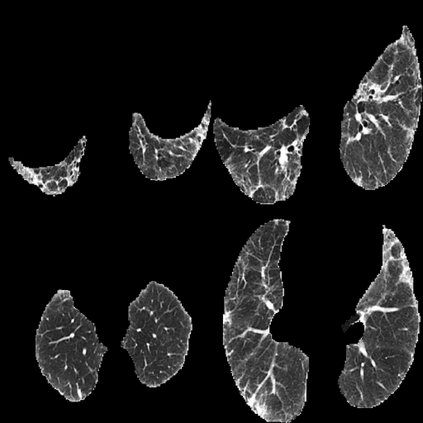

In the field of medical imaging, particularly in tasks related to early disease detection and prognosis, understanding the reasoning behind AI model predictions is imperative for assessing their reliability. Conventional explanation methods encounter challenges in identifying decisive features in medical image classifications, especially when discriminative features are subtle or not immediately evident. To address this limitation, we propose an agent model capable of generating counterfactual images that prompt different decisions when plugged into a black box model. By employing this agent model, we can uncover influential image patterns that impact the black model's final predictions. Through our methodology, we efficiently identify features that influence decisions of the deep black box. We validated our approach in the rigorous domain of medical prognosis tasks, showcasing its efficacy and potential to enhance the reliability of deep learning models in medical image classification compared to existing interpretation methods. The code will be publicly available at https://github.com/ayanglab/DiffExplainer.